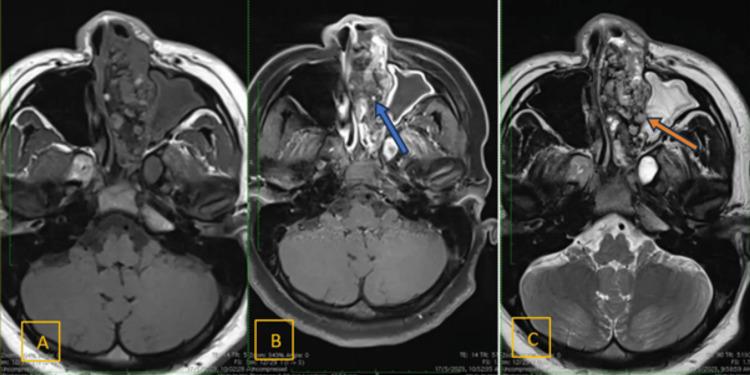

Adamantinomatous craniopharyngioma (ACP) is one of the two types of craniopharyngioma recognized by the World Health Organization (WHO), the other being papillary craniopharyngioma (PCP). These rare, benign tumours of the pituitary region are classified as Grade 1 central nervous system (CNS) tumours. ACP predominantly affects adolescents aged 5-15 years and adults over 50 years. It is usually located in the sellar and suprasellar regions. We present the case of an 18-year-old Malaysian female with a six-year history of persistent epistaxis and progressive nasal obstruction, an atypical presentation of ACP. This report highlights an entirely ectopic location of ACP in the sinonasal region. The tumour encompassed the left nasal cavity, the left anterior and posterior ethmoid sinuses, and the bilateral frontal sinuses. The unusual presentation of this tumour was detected with the aid of CT and MRI and confirmed by histopathological examination. In this case report, we discuss a rare presentation, an unusual location, and the strategies employed to overcome these challenges.

造釉细胞瘤型颅咽管瘤(ACP)是世界卫生组织(WHO)认可的两种颅咽管瘤类型之一,另一种是乳头型颅咽管瘤(PCP)。这些罕见的垂体区良性肿瘤被归类为1级中枢神经系统(CNS)肿瘤。ACP主要影响5至15岁的青少年和50岁以上的成年人。它通常位于鞍区和鞍上区。我们报告一例18岁马来西亚女性病例,有六年持续性鼻出血和进行性鼻塞病史,这是ACP的非典型表现。本报告强调了ACP在鼻窦区域完全异位的位置。肿瘤累及左侧鼻腔、左侧前后筛窦和双侧额窦。借助CT和MRI检测到该肿瘤的异常表现,并经组织病理学检查证实。在本病例报告中,我们讨论了一种罕见的表现、不寻常的位置以及为克服这些挑战所采用的策略。